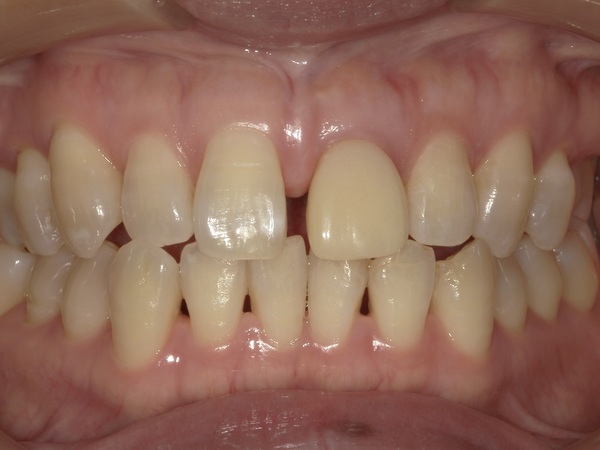

インプラントと骨がしっかり結合するのを待ち、型取りを行い、インプラントに仮歯をセットしました。もともと正中離解(すきっ歯)のため、まずは元の形に近い状態で仮歯を入れました。

④仮歯の調整

患者様に右上の歯を削らずにコンポジットレジン(CR)で幅を少し大きくし、すきっ歯を改善する方針を提案させていただきました。こちらがコンポジットレジン修復を行い、仮歯を調整後の写真となります。左右の歯に多少の大きさの差はありますが、こちらの方がより審美的に良いかと思います。